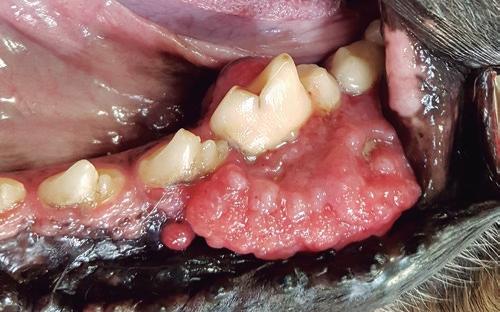

En cuanto al aspecto clínico, el AAC se presenta como un engrosamiento que puede originar desplazamiento dental e incluso mala oclusión en el animal, si bien es un proceso indoloro y de expansión lenta. Puede presentarse como un ameloblastoma periférico que afecta a los tejidos blandos de la encía o como un ameloblastoma central o intraóseo que se origina en el interior del hueso mandibular.

biológico es independiente de la apariencia macroscópica. Sí que podemos encontrar variación en cuanto a la sintomatología, que depende fundamentalmente de la localización y de la extensión del tumor dentro de la cavidad oral. Algunos signos clínicos que podemos ver son:

• Enrojecimiento de la encía.

• Deformidad facial, sobre todo en la mandíbula.

• Sangrado oral: son masas friables que sangran fácilmente y pueden verse restos de sangre en la saliva o en los juguetes.

• Dificultad para comer.

• Dolor o malestar al masticar.

• Dificultad en la aprehensión y/o deglución la comida.

• Movilidad dental, incluso pérdida dental.

• Babeo.

• Halitosis.

En cuanto al aspecto clínico, el AAC se presenta como un engrosamiento que puede originar desplazamiento dental e incluso mala oclusión en el animal, si bien es un proceso indoloro y de expansión lenta.

En su aspecto visual podemos encontrar algunas variaciones: algunos tumores pueden ser nodulares o multilobulados (aspecto de coliflor sangrantes al paso de una gasa) (Lassarra, 2012), mientras que otros aparecen como una masa infiltrativa difusa. A pesar de esto, el comportamiento

• Se inicia como un crecimiento visible en las encías.

• A menudo tiene un aspecto irregular y sangrante.